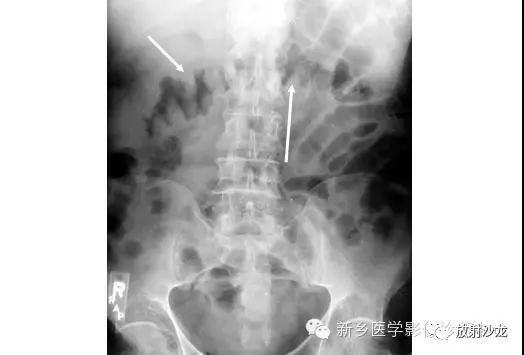

上图腹部平片检查是一6岁男孩,出现呕吐和急性右髂窝疼痛进行的。两个关键的发现在哪里?(提示:通过放射科医生所提供的箭头可以缩小关注点。)

右髂窝多个扩张的小肠襻出现小的钙化结节。小肠袢可与大肠区分开来,因为小肠的环状襞延伸至整个肠壁,而结肠袋只是部分延伸存在。在右下腹(箭头)的钙化结节高度提示阑尾粘连。这个病人开腹手术发现阑尾粘连致小肠梗阻。